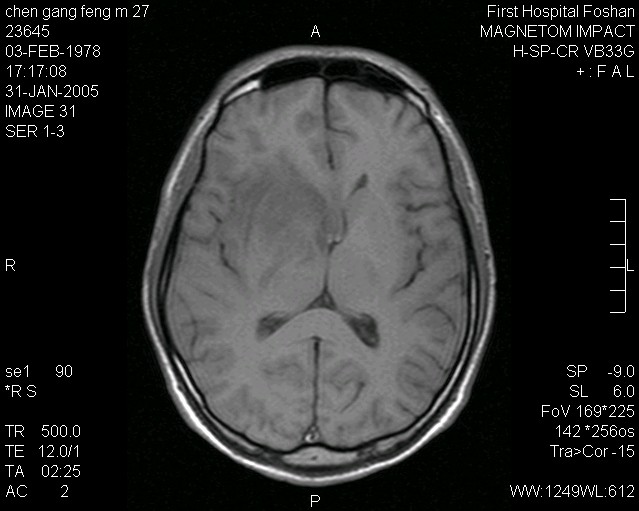

病种:脑胶质瘤

病情:王先生,在今年的一月初,肢体突发抽搐、眼睛上翻,意识丧失,后送到医院。经磁共振检查,发现原右额叶病灶可见轻度斑片状不均匀强化,大小约为2.8X2.4X3.0CM(左右X前后X上下)。余颅内未见强化影。确诊为脑胶质瘤。

结果:后来就在医院,做了手术。术后刚刚感觉效果还不错,但是过了1个月,肢体又感觉麻木。到医院检查,发现疾病再次复发。后做了射波刀,消除了体内的残余肿瘤,目前患者自己能够行走,抽搐少量很多,肿瘤已经找不到,没有再次复发。